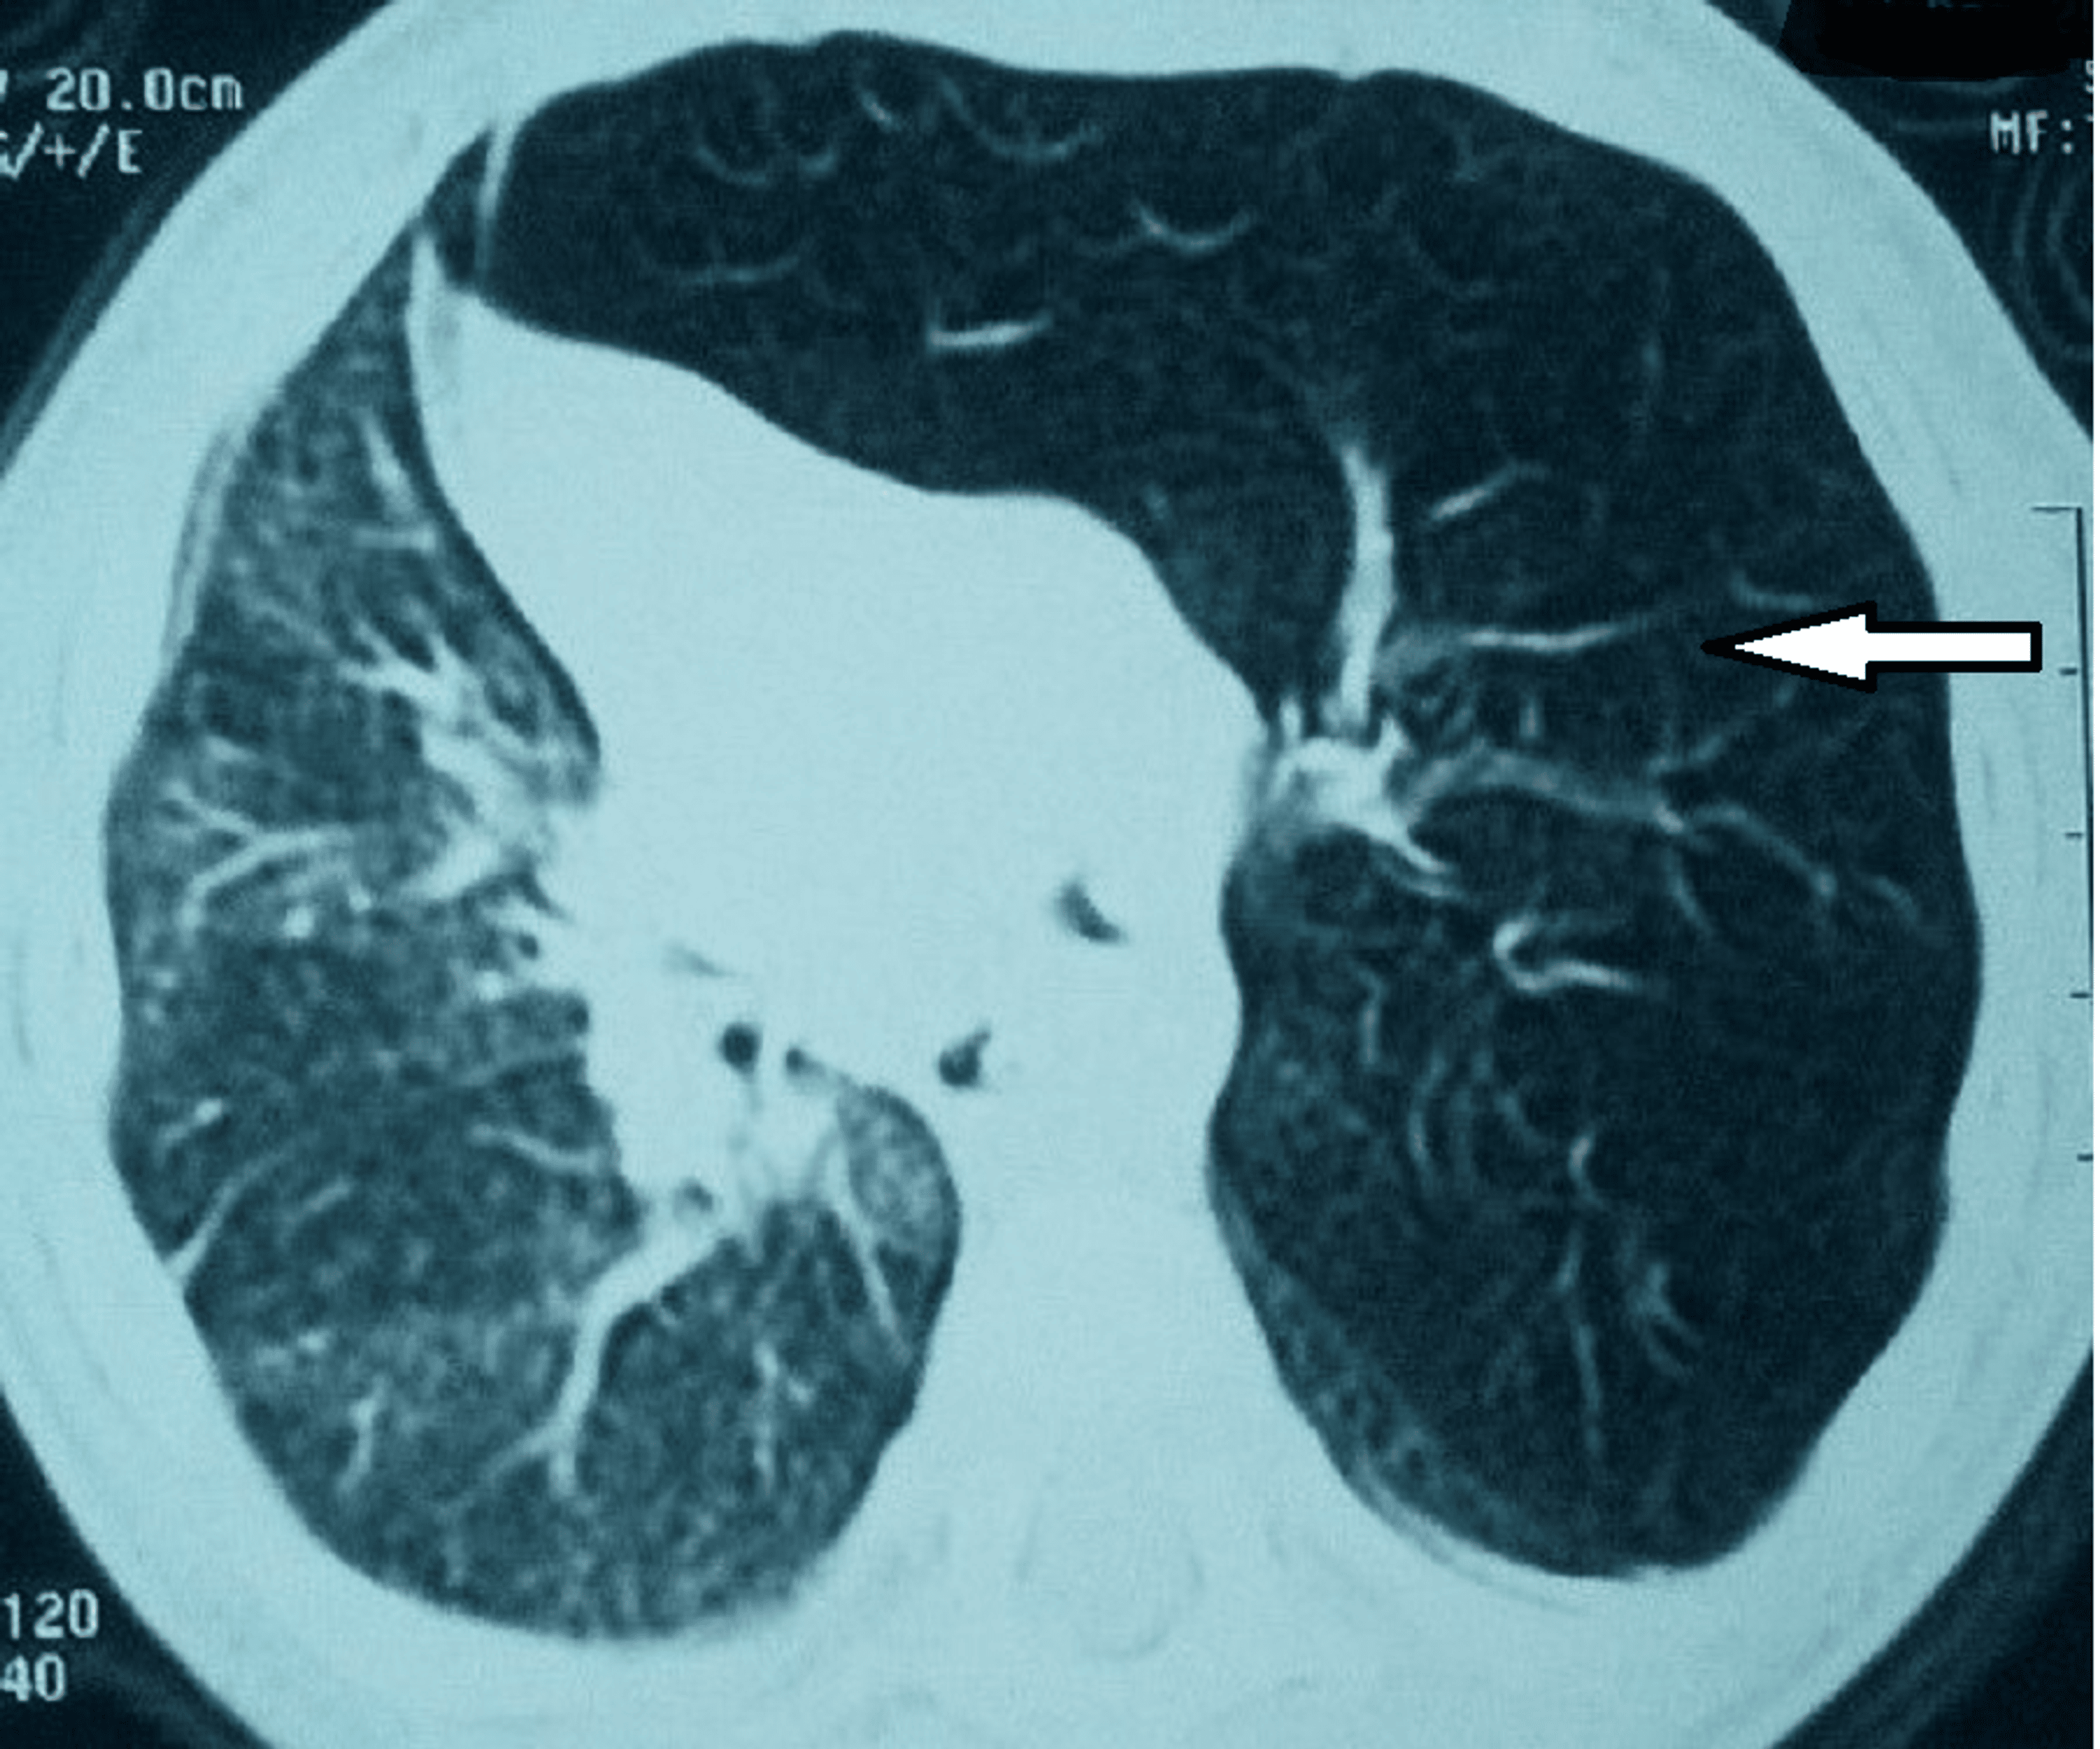

(PDF) Spontaneous pneumothorax and bullous emphysema in a young patient Youngest Emphysema Case Using cox proportional model, we determined the comorbidities associated with mortality risk and generated comorbidomes for. Emphysema is a type of. Cases had moderate airflow limitation (fev1 71.3±20.8%) but were often symptomatic, used healthcare resources frequently, had air trapping (residual volume 150.6±55.5% ref.), had reduced. Emphysema can cause chest tightness, shortness of breath, and fatigue. Youngest Emphysema Case.

Case 48 Combined Pulmonary Fibrosis and Emphysema (CPFE) Youngest Emphysema Case Using cox proportional model, we determined the comorbidities associated with mortality risk and generated comorbidomes for. Emphysema can cause chest tightness, shortness of breath, and fatigue. Emphysema is a type of. Cases had moderate airflow limitation (fev1 71.3±20.8%) but were often symptomatic, used healthcare resources frequently, had air trapping (residual volume 150.6±55.5% ref.), had reduced. Youngest Emphysema Case.